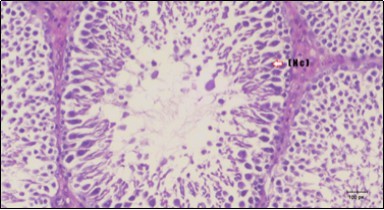

Testis Histopathological Observations

Histological examination of control rats' testis showed normal histological structure of the seminiferous tubules with an increase in the spermatogonia and other spermatocytes compared with the diabetic rats which showed an obvious decrease in the count of germinal cells generally and sloughing of germ cell in the lumen of seminiferous tubules in addition to absence of the mature sperms (Figure 3 and Figure 4). Rats tested of Fenugreek group and those treated with Glimepiride (Figure 5 and Figure 6) presented an increase in the number of spermatogenic cells and mature sperms with few focal necrotic cells. Whereas the combination therapy group showed normal histological structure of the seminiferous tubules with normal spermatogonia, presence of ledying cells and more mature of sperms (Figure 7). STZ reduced testosterone production, suggesting a decrease in the function of both Leydig (testosterone producing cell) and Sertoli (spermatogenesis) cells, which might be caused by a reduction in insulin secretion. These changes are probably due to increased Reactive Oxygen Species (ROS) production by accelerated Advanced Glycation End Products (AGE) formation 31 hexosamine and Protein Kinase C pathway. The administration of Fenugreek seeds to diabetic rats significantly decrease of sperm shape abnormality and improve the sperm count 32. Glimepiride reduced sperm abnormality and increased testis weights and sperm count by its antioxidant action 30. The potential protective efficacy of Fenugreek seed extract when added to Glimepiride was observed on reproductive systems.

Figure 3.Photomicrogragh of testis section of a control rat showing testicular tissue with seminiferous tubules separated by interstitial tissue with Ledying cells (arrow). Seminiferous tubules with complete spermatogenesis, Sertoli cell (dashed-arrow) and spermatozoa . (H&E) (40X).